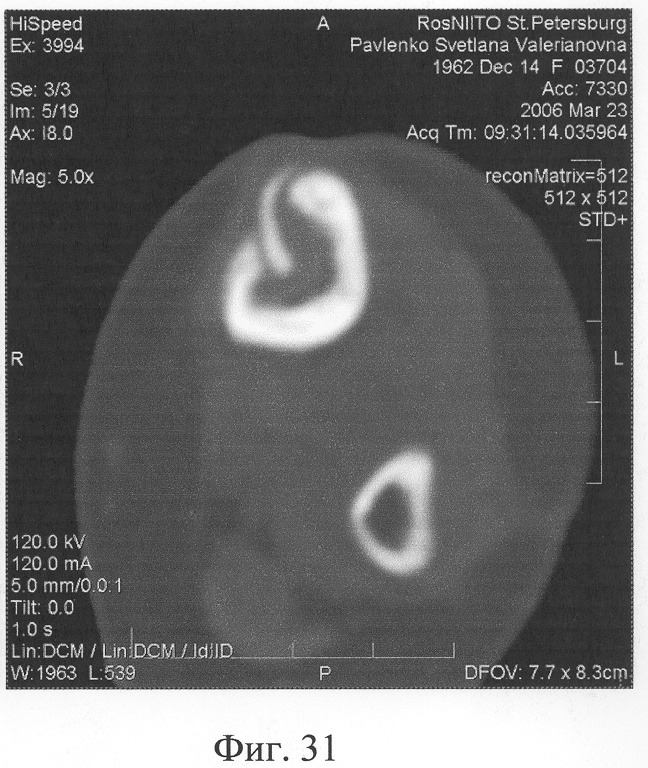

Аппарат внешней фиксации с левой голени демонтирован через 3 месяца после операции при клинико-рентгенологической картине сращения перелома. Аппарат внешней фиксации с правой голени демонтирован через 7 месяцев после операции при клинико-рентгенологической картине сращения перелома (фиг.20-25 – результат лечения). При рентгенологическом и томографическом контроле в трансплантатах отмечалось постепенное нарастание плотности костной ткани с формированием костной мозоли на всем протяжении между трансплантатом и костными фрагментами (фиг.26-29 – динамика данных компьютерной томографии правой голени: отмечается нарастание плотности костной ткани в области трансплантатов и формирование регенерата между смещенным трансплантатом и костными фрагментами; фиг.30-33 – динамика данных компьютерной томографии левой голени: отмечается нарастание плотности костной ткани в области трансплантатов и формирование регенерата между трансплантатом и костными фрагментами).